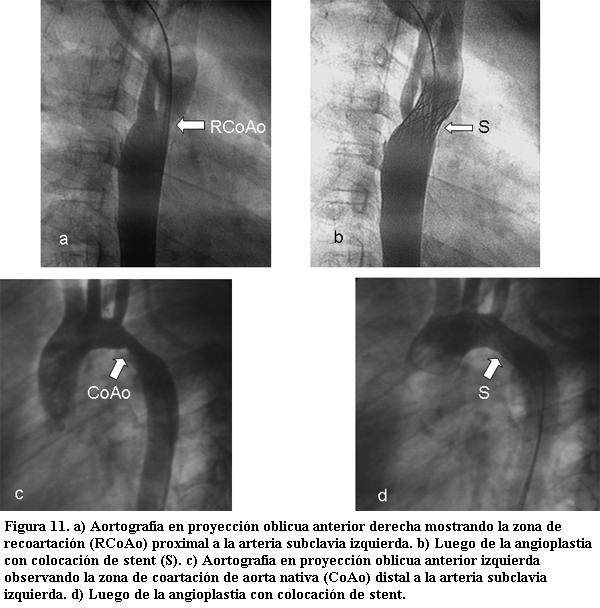

La angioplastia de la coartación de aorta (CoAo) involucra dos entidades: 1) CoAo nativa, y 2) CoAo postoperatoria o lesión residual (recoartación).

Respecto al tratamiento percutáneo de la coartación de aorta nativa existen dos indicaciones: 1) Coartación de aorta en el recién nacido o lactante, como lesión aislada o en el contexto de una cardiopatía congénita compleja, que se presente con inestabilidad hemodinámica, lo cual determina un elevado riesgo quirúrgico, permitiendo a angioplastia la estabilización del paciente y posterior tratamiento quirúrgico; 2) Coartación de aorta en el niño mayor y/o adolescente con buena anatomía (lesión circunscrita, centrada, con buen sector aórtico proximal y distal) donde puede considerarse un procedimiento curativo, con o sin la utilización de stents (cuyo uso es obligatorio en caso de persistencia de un ductus permeable o frente a la asociación de un aneurisma).

La recoartación de aorta (poscorrección quirúrgica o postangioplastia de una CoAo nativa previa, con o sin colocación de Stent) tiene indicación formal de ser tratada con catéter balón (63-67).

A excepción del tratamiento paliativo en neonatos, el procedimiento está indicado frente a la presencia de un gradiente de presiones entre miembros superiores y miembros inferiores en reposo superior a los 20 mmHg y con un peso superior a los 30 kilos.

El tratamiento por vía percutánea se basa en la dilatación con catéter balón y en el eventual implante de stent como forma de disminuir los riesgos de reestenosis y de aneurismas. En la actualidad han aparecido los stents recubiertos los cuales tienen clara indicación en el tratamiento de aquellas coartaciones con estrechamientos muy severos, que asocian otra patología como ser un ductus permeable o un aneurisma, o corresponden a angioplastias previas (con o sin stent) donde el riesgo de lesionar la pared aórtica es muy elevado (68,69).

Los diámetros de los balones a utilizar deben tener una relación 1:1 con respecto al diámetro de la porción horizontal del cayado aórtico.

Los resultados son exitosos en más del 95% de los casos, con una ventaja adicional, frente al tratamiento quirúrgico, que consiste en que la mayoría de los pacientes tratados por vía percutánea que quedan sin gradiente significativo de presiones no presentan, en general, el fenómeno de la hipertensión paradojal. Las complicaciones descritas con esta técnica son: la aparición de aneurismas (5%) y la reestenosis (3%-7%), ambas en casos de angioplastia aislada sin el uso de stents; y la hipertensión arterial residual (20-50% en diferentes series) en caso de quedar un gradiente residual significativo siendo observada con mayor frecuencia cuanto mayor sea la edad del paciente al momento de la angioplastia (tablas 7 y 8, figura 11) (70-73).